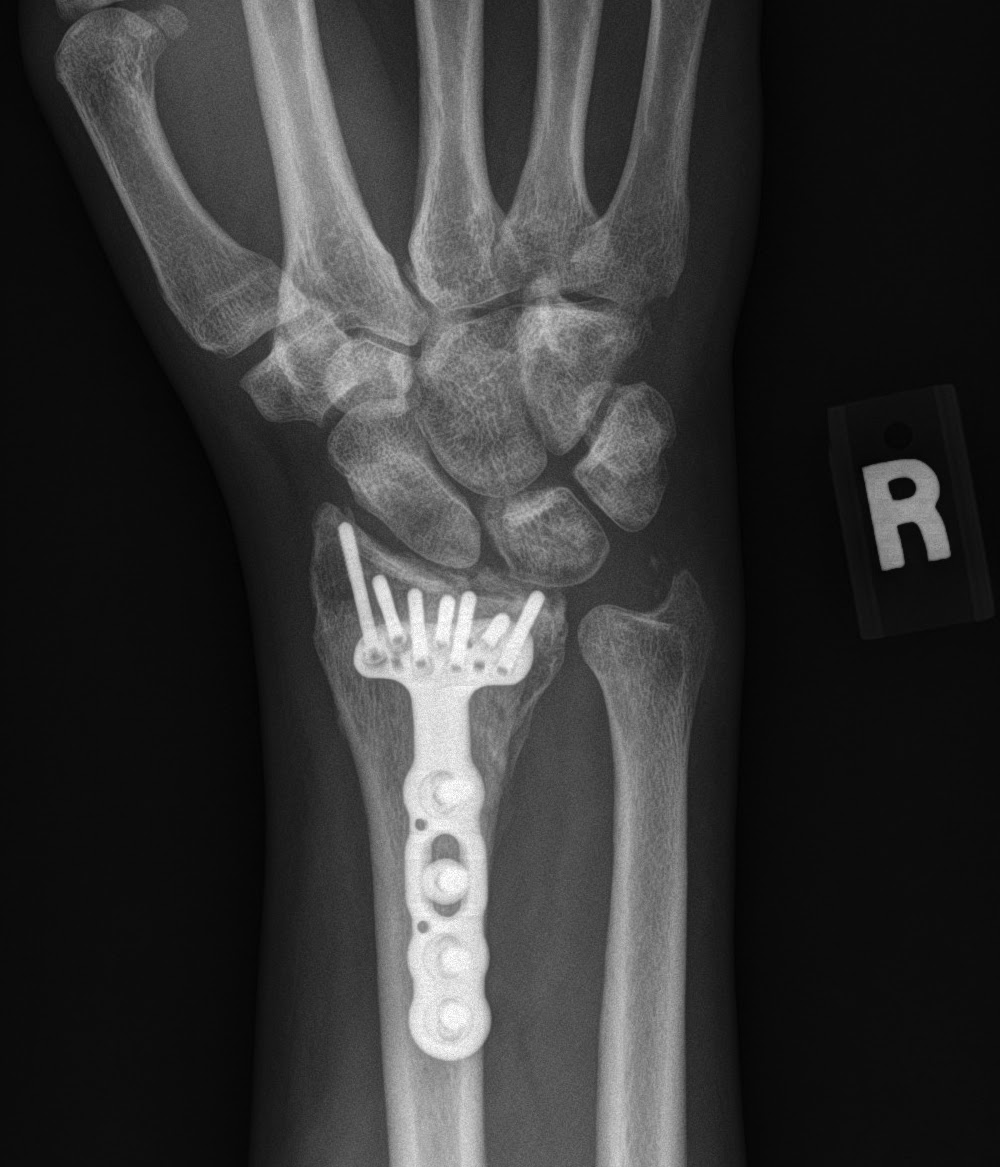

Артродез кисти

Артродез кисти 114 фотографий